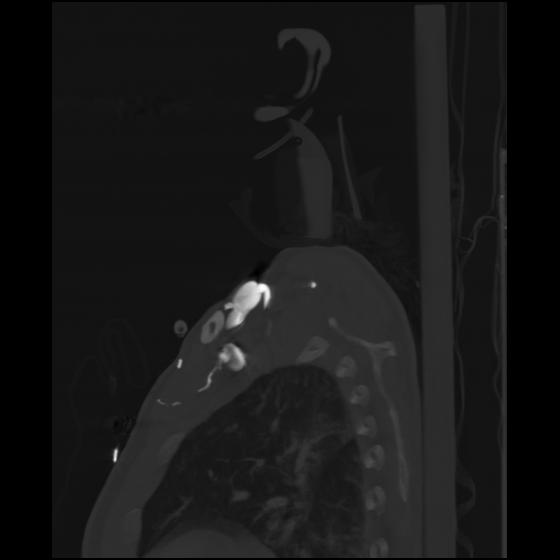

24 ANGIO,CE,Sag-MIP,5.000,ANGIO,Sag-MIP,